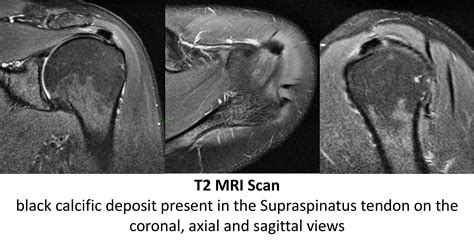

MRI Rarely needed, but used if doctors need to rule out rotator cuff tears or other structural damage.